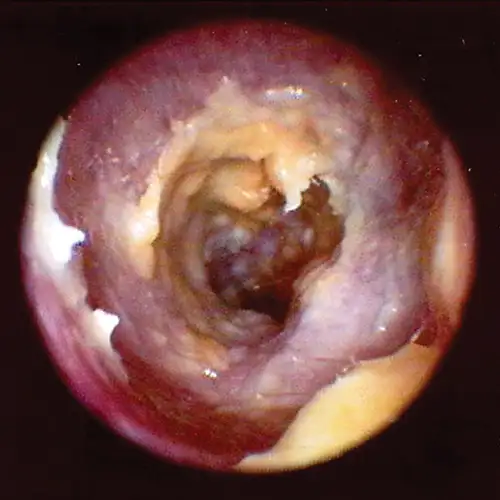

Globoid brown-to-black mass occluding internal ear canal.

FIGURE 14

Wax plug (ceruminolith) on the eardrum

Wax plug in an ear. Accumulations of wax (cerumenolith) commonly  show up at the eardrum when the eardrum epithelial surface has been previously compromised.  Dried oily medication and inspissated mucus from the bulla can look similar.

Cerumen accumulation against the eardrum, in addition to stenosis and hyperplasia, can impede conduction of sound waves and result in temporary hearing loss. Ceruminoliths require mechanic removal, preferably with endoscopic grasping forceps through a video otoscope with the patient anesthetized. If the eardrum is not intact, exudates such as mucus and pus can leak into the horizontal canal and inspissate at the eardrum. This condition can look like a ceruminolith. The mucoid secretions dissolve in water and can be removed with a water or saline flush of the horizontal canal.